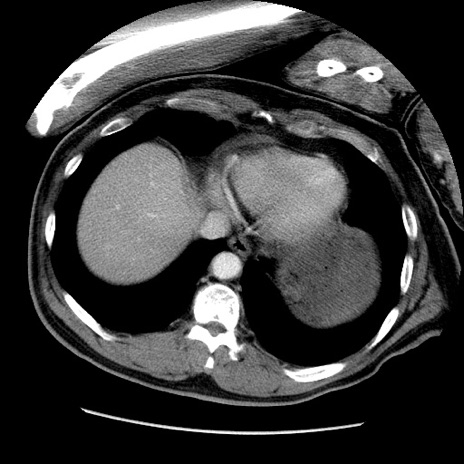

症例22(横断像)

【症例】50歳代男性

【主訴】腹痛

【現病歴】AVMからの被殻出血のため回復期リハ病棟入院中。 本日午後3時頃急に下腹部痛が出現した。

【既往歴】AVM、被殻出血、虫垂炎、高血圧

【身体所見】意識晴明、左半身不全麻痺、会話の理解は良好、36.5°C、腹部:膨隆、全体に板状硬、下腹部正中に圧痛点あり、反跳痛-、筋性防御不明、右下腹部にope scar

【データ】WBC 9400、CRP 0.06